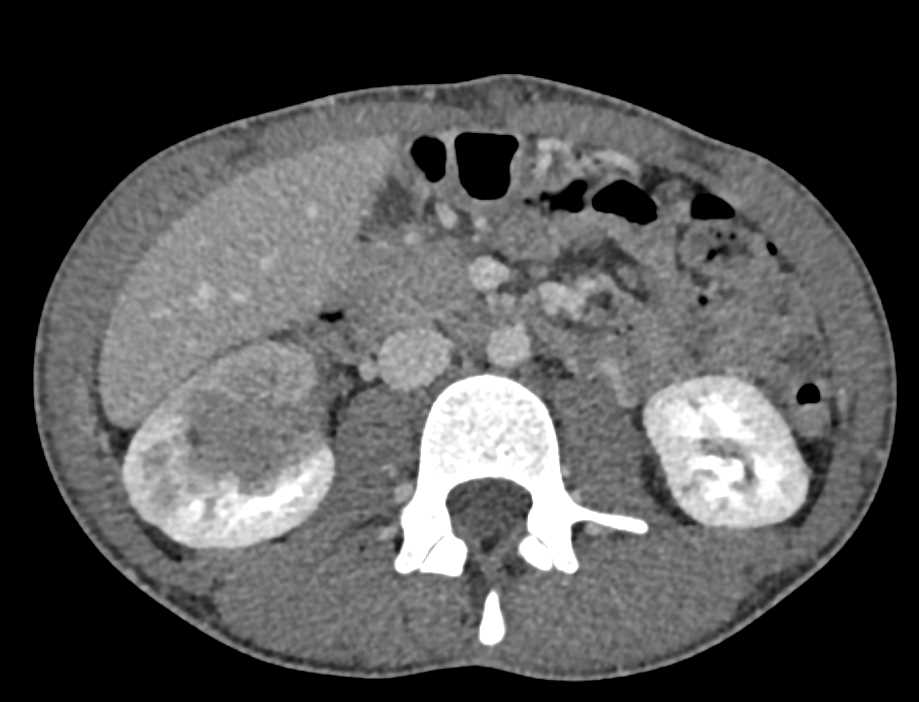

Metastatic Renal Cell Carcinoma